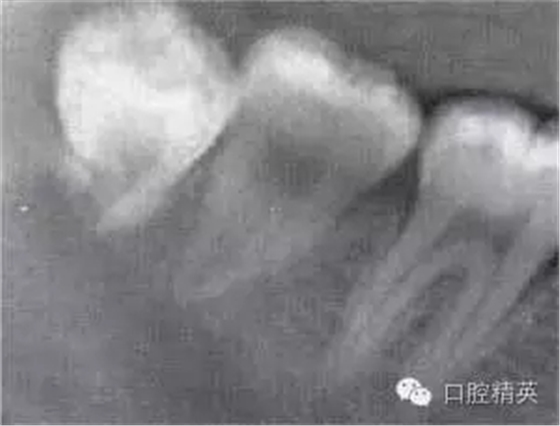

圖6-5 以上類型的下頜第三磨牙由于根阻力小,一般不需分根,即可拔除。

A.合并根 B.短根 C.椎形根 D.牙根向遠(yuǎn)中彎曲 E.根分叉小 F.根尖未完全形成